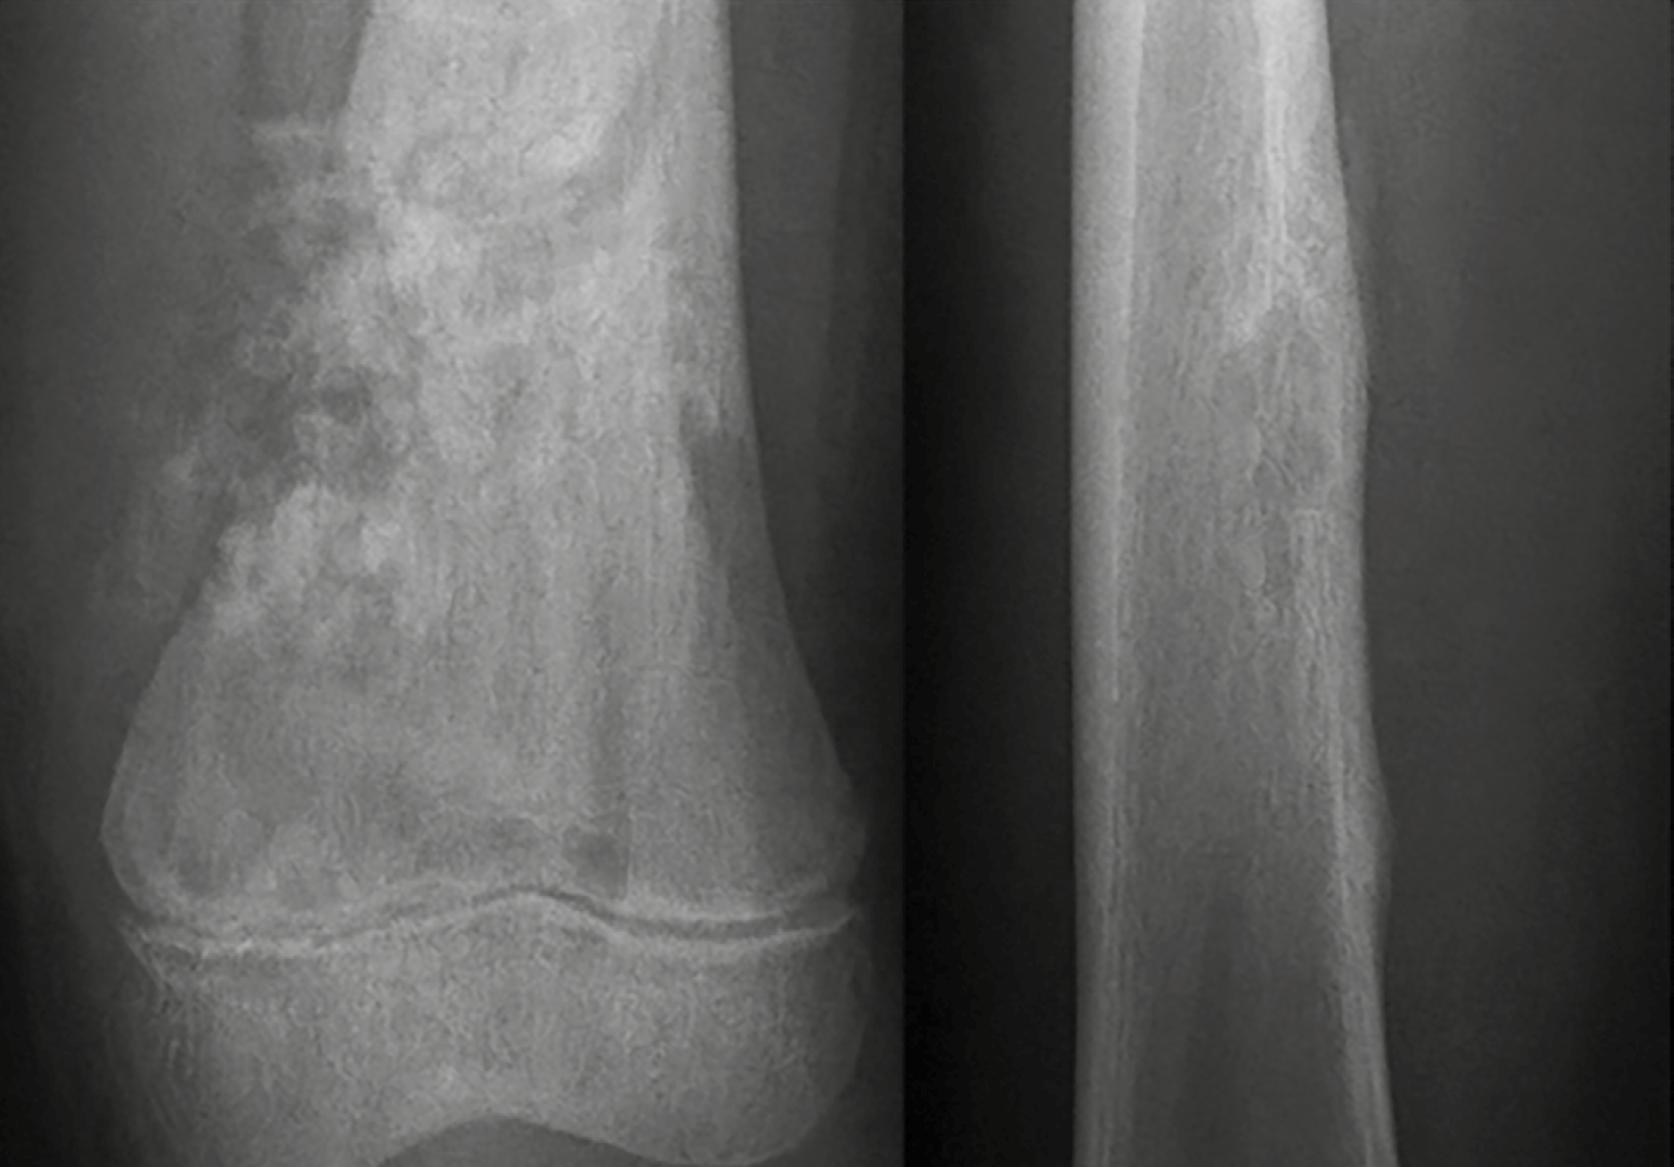

Se refiere al límite entre el hueso sano y la lesión. Una transición bien definida suele asociarse con lesiones benignas, mientras que los márgenes mal definidos tienden a sugerir comportamiento agresivo o maligno. Para interpretar correctamente una lesión osteolítica, uno de los aspectos clave es evaluar la zona de transición entre la lesión y el hueso sano circundante. Esta zona actúa como un indicador fundamental para diferenciar entre procesos benignos y malignos. Las lesiones bien definidas, con bordes nítidos y una transición estrecha, suelen indicar un crecimiento lento y comportamiento biológico no agresivo. En algunos casos, incluso se puede observar un borde esclerótico, lo que refuerza la idea de una lesión inactiva. Sin embargo, en pacientes mayores de 30 años, y especialmente en mayores de 40, no se puede descartar la posibilidad de metástasis o plasmocitoma, incluso si las imágenes sugieren benignidad. En la Figura 2 , por ejemplo, se muestran tres lesiones con zona de transición estrecha en pacientes pediátricos, cuyas placas de crecimiento aún no se han cerrado, lo cual refuerza el diagnóstico de lesiones benignas.

Figura 2. Zona estrecha de transición. 1. Fibroma no osificante. 2. Quiste óseo simple. 3. Quiste óseo aneurismático. Tomada de: Jan van der Woude R, Smithuis R. Bone tumors. Differential diagnosis [Internet]. 2010 [consultado 2025 oct 13]. Disponible en: https://radiologyassistant.nl/ musculoskeletal/bone-tumors/differential-diagnosis